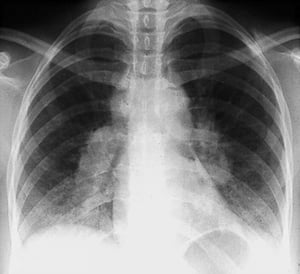

Sarcoidosi (stadio IV)

Grave fibrosi diffusa con adenopatia ilare e alterazioni cistiche dei lobi superiori nella sarcoidosi allo stadio IV.

By permission of the publisher. From: Tanoue L, Elias J. In Bone's Atlas of Pulmonary and Critical Care Medicine. Edited by J Crapo. Philadelphia, Current Medicine, 2005.